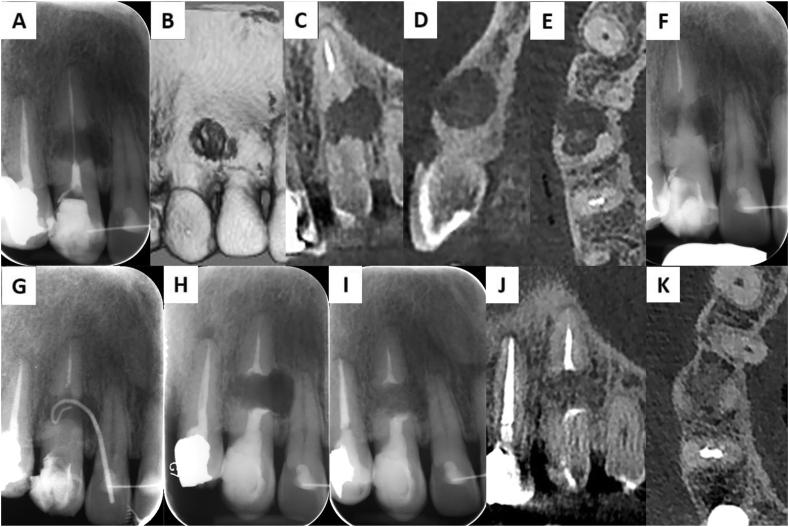

Management of an unrepairable root perforation due to inflammatory root resorption: A case report.

https://cdn.ncbi.nlm.nih.gov/pmc/blobs/ec02/9236960/e992495fe006/gr1.jpg